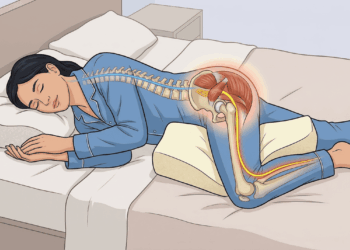

Existe ainda a tosse noturna, que piora ao deitar, frequentemente associada ao refluxo ou ao gotejamento de secreção nasal na garganta. E a tosse que vem acompanhada de um som agudo, semelhante a um “guincho”, pode ser sinal de coqueluche, uma infecção bacteriana que voltou a preocupar autoridades de saúde em diversos países.

O ácido do estômago pode subir até a garganta e causar tosse seca, piorando após refeições e à noite.